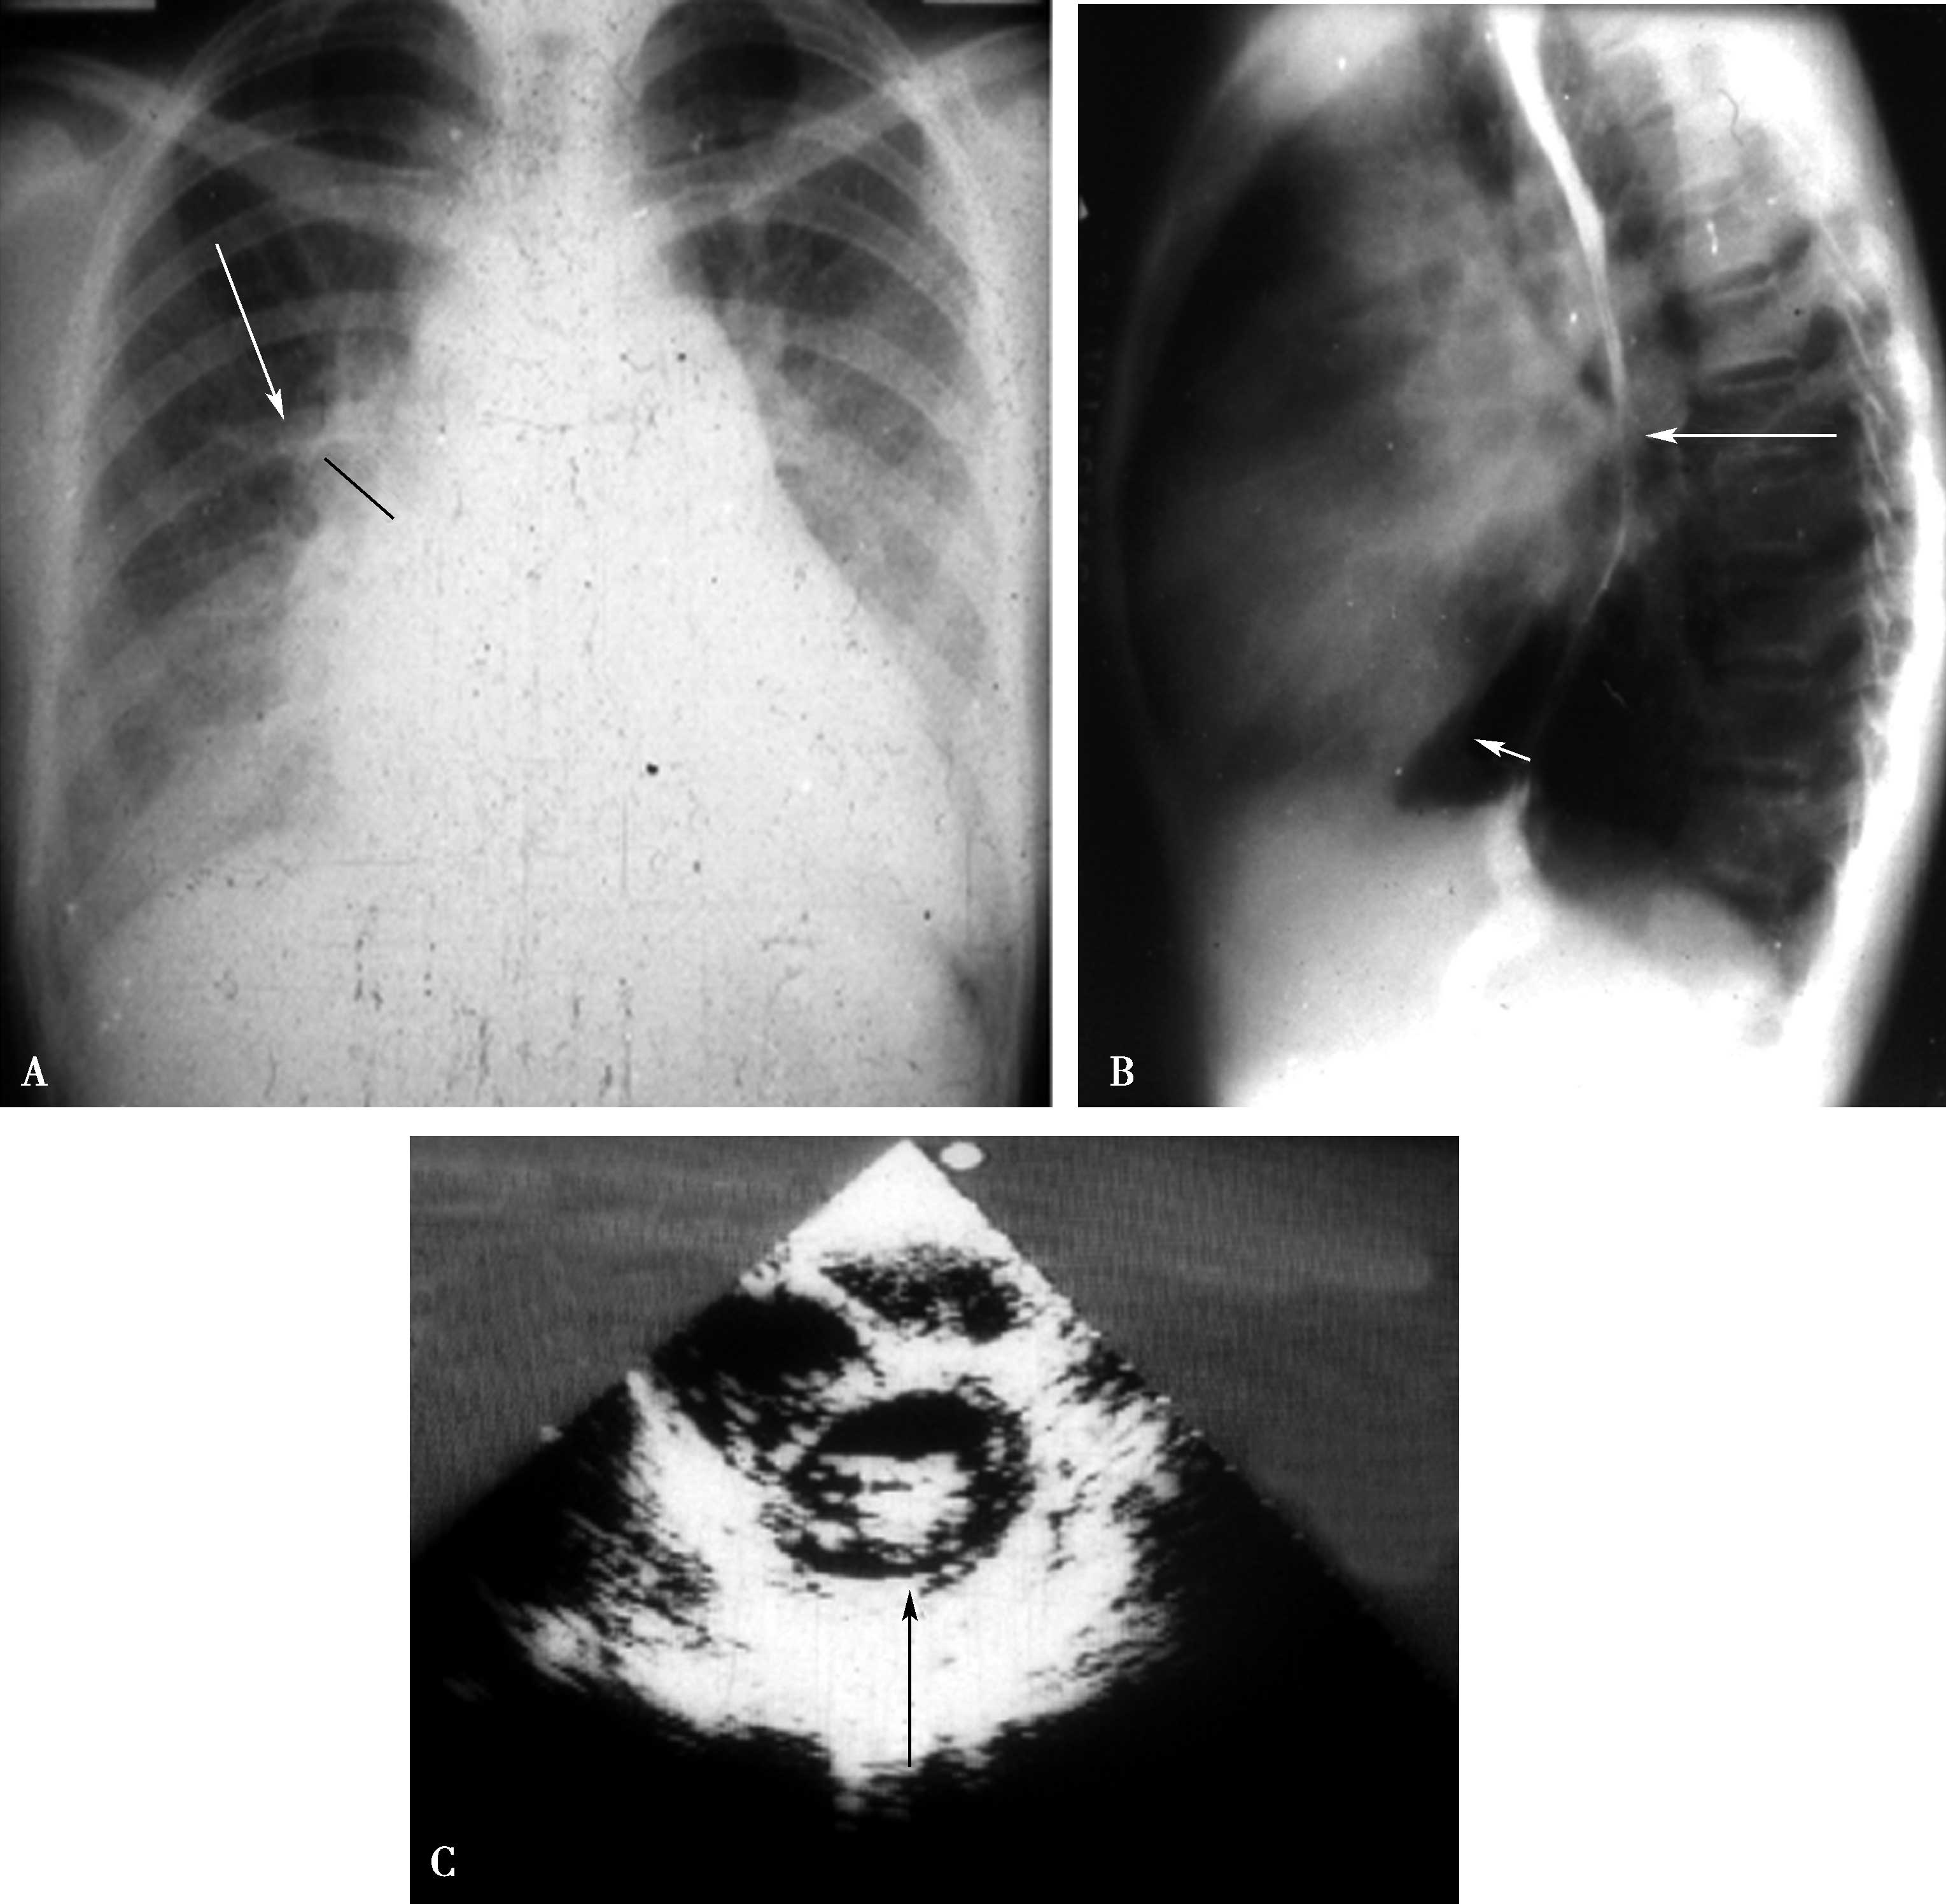

(二)左心室增大(图7-1-3)

1.远达片

左心室缘向左膨隆、向下延伸,心尖下垂可达左膈下(图7-1-3A↑)。

2.左前斜位

心脏后下缘向后膨隆,心后间隙消失,后室间沟下移(图7-1-3B↑)。

3.左侧位

心脏后下缘向后膨隆,心后间隙消失(图7-1-3C↑)。

图7-1-3 左心室增大征象

A.远达片;B.左前斜位;C.左侧位

(三)右心房增大(图7-1-4)

心脏右缘(右心房段)向右、上膨隆;右心房高度增大、相反搏动点上移(图7-1-4A↑)。

心前缘向右、上膨隆,心前间隙缩小,如果右心室增大不相称,心前缘有成角现象(图7-1-4B↑)。

3.右前斜位

心后缘向后膨隆,与服钡食管仅是重叠无推移现象(图7-1-4C↑)。

图7-1-4 右心房增大征象

A.远达片;B.左前斜位;C.右前斜位

(四)右心室增大(图7-1-5,图7-1-6)

心脏左右缘膨隆;心尖圆隆、上翘;肺动脉段及圆锥部膨隆(图7-1-5A↑)。

心前缘向前膨隆,心-膈面延长,心前间隙缩小;后室间沟上移(图7-1-5B↑)。

心前缘向前膨隆,心前间隙缩小,肺动脉圆锥部膨隆(图7-1-5C↑)。

4.左侧位

心前缘向前膨隆,心前间隙缩小,肺动脉圆锥部膨隆(图7-1-5D↑)。

图7-1-5 右心室增大征象

A.远达片;B.左前斜位;C.右前斜位;D.左侧位

图7-1-6 右心房、室增大征象 右心房增大(↑),右心室增大(▼)